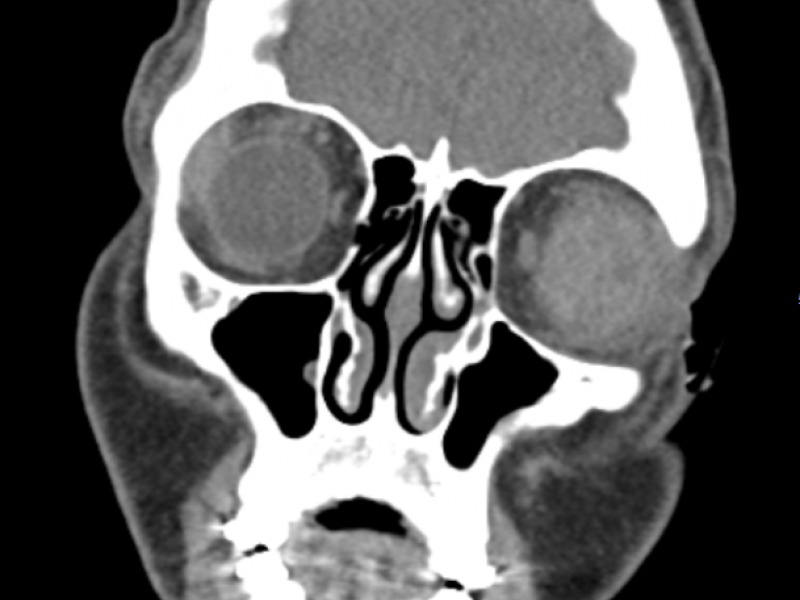

An 18 yo M presents to the ED after being hit in the L eye